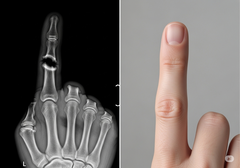

Сращивание позвонков - это распространенная процедура лечения изнурительной боли в спине путем соединения двух или более позвонков, однако она может иметь высокий процент неудач. Существующие методы лечения часто опираются на костные трансплантаты или мощные факторы роста, которые иногда могут привести к осложнениям, например, к неконтролируемому образованию костной ткани за пределами целевой области.

В основе подхода Bone Biologics лежит белок NELL-1, фактор роста, который естественным образом участвует в развитии костей. Доклинические исследования показали, что NELL-1 обладает уникальной способностью стимулировать интенсивный рост костей именно там, где это необходимо, и одновременно подавлять образование жировых клеток, что является общей проблемой для других биопрепаратов. Такое целенаправленное действие может привести к более надежным сращениям и меньшему количеству осложнений.